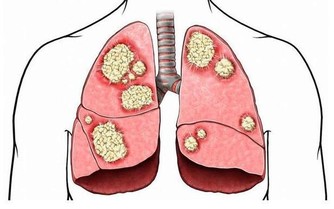

圖片來源:衛生福利部粉專2020-02月武漢肺炎(新型冠狀病毒肺炎)疫情擴大,加上最近的寒流冷颼颼,讓病毒存活率又更高了~為了自己跟他人的健康安全著想,想要有效防止武漢病毒大擴散,養成「戴口罩」的習慣真的好重要,口罩不離口鼻,並要勤洗手,這兩點最為關鍵!!

面對愈來愈嚴重的空氣污染,許多人都會使用口罩,你應該也戴過,但是你知道戴口罩的目的、功能嗎?面對市面上所販售的多種口罩,你會挑選符合自己需求的嗎?以下我們將就口罩進行探討。

市面上常見的口罩大概分為以下幾種:外科手術口罩、N95口罩、棉布口罩、海綿口罩等。其中常見的綠色口罩是醫療級的外科口罩,三層設計能有效阻隔細菌與病毒,避免我們透過口鼻將細菌吸入體內。N95口罩能有效阻隔空氣傳播的病菌病毒,缺點是透氣度低,不適合常戴,而政府也表示,現階段的防疫無需配戴N95口罩。其餘像是常見的可洗式棉布口罩或是活性碳口罩等,只能阻隔大型灰塵及異物,或是花粉、塵埃、霧霾,此時都無法阻隔經由口沫傳染的新型冠狀病毒。